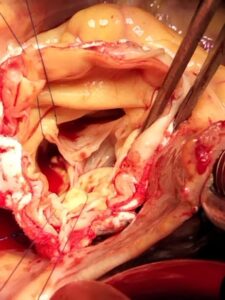

There are several approaches to complex aorta surgery, depending on the specific problem. The surgery is typically performed by a cardiovascular surgeon and can be done in different ways: